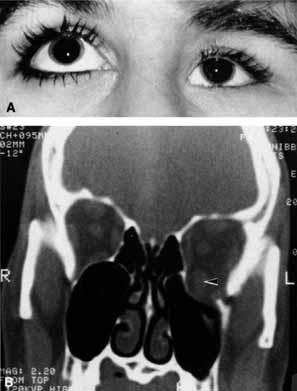

OPTIC NERVE The tempo and character of vision loss can be important diagnostically. The tempo of visual acuity deterioration varies from optic nerve tumors with characteristically chronic and progressive loss to that of cellulitis or idiopathic orbital inflammation which may be apoplectic. Characteristics of visual change are also important; for instance, gaze-evoked vision loss is most commonly associated with intraconal tumors such as [MT1]optic nerve meningiomas or cavernous hemangiomas.6 This symptom may also occur in patients with orbital fractures, intraconal foreign bodies, or extraconal tumors that compress the central retinal artery.7,8 Transient obscurations of vision, a fleeting blurring of vision lasting seconds, may be associated with papilledema.9 This symptom can be differentiated from amaurosis fugax (complete loss of vision of moderate duration), which is more likely to be secondary to embolic occlusion of the ophthalmic or central retinal artery.10 Every patient with a suspected orbital abnormality deserves a complete eye examination, whether he or she needs it or not.11 Visual acuity with current correction, a manifest refraction, and a cycloplegic refraction are important to detect induced hyperopia from an intraconal tumor. A rough approximation is 3 D of induced hyperopia for each millimeter of globe shortening. Evaluation of afferent visual function should include tests of color vision, relative afferent pupillary defect, and visual field. Ophthalmoscopy can be very helpful in orbital diagnosis. Optic disc edema may be caused either by papilledema (increased intracranial pressure) (Fig. 11A), papillitis (anterior optic neuritis) (Fig. 11B), or vasculitis (e.g., lupus erythematosus, sarcoidosis, Wegener's granulomatosis, and giant cell arteritis) (Fig. 11C).12 Papilledema (Fig. 11A) is usually present with near-normal visual function, although some patients may lose vision.9 In contrast, papillitis (Fig. 11B) characteristically leads to reduced visual function, commonly is associated with orbital pain, and is associated with inflammatory cells in the vitreous overlying the disc. Optic disc vasculitis (Fig. 11C) may be present with other findings of vasculitis, and commonly is associated with poor acuity and evidence of vascular occlusion (e.g., cotton-wool spots, hemorrhages). The differential diagnosis of the swollen, erythematous disc is discussed elsewhere in these volumes. Optociliary shunts (Fig. 12A) develop as a result of long-term obstruction of the central retinal vein. This may occur secondary to optic nerve meningiomas,13 optic nerve gliomas,14,15 optic nerve meningoceles,16 central retinal vein occlusions,17 optic nerve sarcoidosis,18 craniosynostosis,19 optic nerve arachnoid cysts,20 optic disc drusen,21 and papilledema.15 Congenital optociliary shunts, which are exceedingly rare, have not been associated with optic neuropathy or orbital disease.22,23 The presence of optic nerve pallor, poor acuity and optociliary shunts generally implies an optic nerve meningioma in the absence of other funduscopic findings (Fig. 12B).13 Visual field testing can also be helpful in diagnosis of orbital processes. Optic disc–associated visual field changes are usually altitudinal because of the structure of the horizontal raphé (Fig. 13). This visual field defect is typically a result of anterior ischemic optic neuropathy (AION).24 Compressive lesions of the orbit or retrobulbar inflammation are more likely to produce a central or cecocentral scotoma. However, one must be aware that there is a significant degree of overlap between various types of optic nerve lesions and visual field abnormalities.25 In these cases, neuroimaging may be a useful adjunct in differentiating between different neuro-ophthalmic and orbital processes.26 The relationship of visual function to orbital findings often helps in the differential diagnosis. For instance, patients with cavernous hemangiomas may have significant proptosis but retain normal, best-corrected visual function (see Fig. 7B), but patients with intrinsic optic nerve meningiomas may demonstrate minimal proptosis with significant vision loss (see Fig. 12B). Trigeminal Sensation Historically, the progression of numbness may be helpful in diagnosis of orbital disease. For instance, adenoid cystic carcinoma of the lacrimal gland27,28 and some melanomas29 have a predilection for perineural invasion. The presence of a lacrimal gland mass, which is followed by numbness in the distribution of the lacrimal (see Fig. 2), zy-gomaticotemporal, or zygomaticofacial nerves (Fig. 9), can indicate perineural extension of an adenoid cystic carcinoma. Corneal sensation should always be tested prior to anesthetizing the cornea for applanation tonometry. Corneal sensation can be roughly quantified using an anesthesiometer; however, asymmetry of corneal sensation may be the most important finding in unilateral orbital disease. A cotton wisp, pulled from a cotton-tip applicator, is lightly drawn from the conjunctiva across the limbus onto the cornea. The blink should occur with corneal but not conjunctival touch. Sensory testing of cranial nerves V1 and V2 with the cotton wisp can be performed at the same time. The cutaneous distribution of the zygomaticofacial and zygomatico-temporal branches should not be ignored (see Fig. 9). The upper teeth should also be tested by tapping with the cotton-tip applicator stick, comparing right to left sides and the front teeth to the molars. Blowout fractures that involve the infraorbital nerve commonly result in numbness of the upper teeth because the anterior and middle superior alveolar nerves arise from the infraorbital nerve within the infraorbital canal (see Fig. 10). However, because the posterior superior alveolar nerve arises from the infraorbital nerve before it enters the infraorbital canal, if the molars are also numb, one must consider the possibility of an associated basilar skull fracture. Pain is a helpful diagnostic symptom. There are five types of pain associated with the eye and orbit11,19,30:

CASE 1 A 70-year-old woman presented with a 6-month history of progressive diplopia and ptosis. She demonstrated complete right third, fourth, and sixth cranial nerve palsies, and hypesthesia of cranial nerve V1 (Fig. 22A). The right pupil was dilated. Computed tomography (CT) disclosed an intracavernous aneurysm (see Fig. 22B). The so-called superior orbital fissure syndrome occurs when an infiltrative, inflammatory, or ischemic event occurs within the superior orbital fissure, but not in the orbital apex.4 A complete superior orbital fissure syndrome occurs when all the neurovascular components passing through the superior orbital fissure are damaged, producing a total ophthalmoplegia, ptosis, and anesthesia of cranial nerve V1 (see Fig. 22A). The pupil may be dilated, miotic, or midposition and fixed, depending on the balance of parasympathetic and sympathetic damage. The superior ophthalmic vein, best seen on CT, may be dilated if venous outflow from the orbit is obstructed. Clues to venous outflow obstruction are increased intraocular pressure, fullness of the upper eyelid, and hyperemia of the deep Tenon's vessels. Ophthalmoscopically, the retinal veins may be dilated. The effect of a lesion in the superior orbital fissure or the anterior cavernous sinus cannot be differentiated clinically (see Fig. 22B). When the posterior cavernous sinus becomes involved, hypesthesia of cranial nerve V2 may also be present. The only difference between a superior orbital fissure syndrome and an orbital apex syndrome is the presence of visual loss caused by optic nerve involvement. Visual acuity, color vision, or the visual field are abnormal. An ipsilateral relative afferent pupil defect is present. CASE 2 A 30-year-old man noted diplopia and right ptosis for the past month. The patient demonstrated normal vision and symmetric pupils but had a neurogenic ptosis (Fig. 23A) and limited right supraduction (Fig. 23B). Otherwise his extraocular movements were full. CT demonstrated an intracranial aneurysm of the posterior communicating artery aneurysm (Fig. 23C). Anatomically, the third cranial nerve branches into its superior and inferior divisions as it enters the orbit through the superior orbital fissure. Superior branch damage results in ptosis (levator muscle) and decreased supraduction (superior rectus muscle). Inferior branch damage results in decreased adduction (medial rectus), decreased infraduction (inferior rectus), decreased excycloduction (inferior oblique), and a dilated pupil (parasympathetic). Anatomically, a cranial nerve III branch nerve lesion seems to imply an anterior cavernous sinus or orbital apex localization. However, functionally, the third cranial nerve may bifurcate in the intracranial portion of the nerve, so cranial nerve III branch nerve palsies have been demonstrated with intracranial lesions. The localizing finding of a cranial nerve III branch nerve lesion is therefore not absolute (see Fig. 23).46 CASE 3 A 12-year-old child was referred by his school nurse because he had been complaining intermittently of double vision and the nurse had noted intermittent right ptosis. The child presented with a right ptosis and limited infraduction of the left eye (Fig. 24A). The ptosis worsened with prolonged up-gaze. A Cogan lid twitch was noted on the right with upward saccades. Injection of 1 mg of edrophonium resulted in complete resolution of diplopia and ptosis (Fig. 24B). The diagnosis was myasthenia gravis. Most orbital and cavernous sinus lesions produce afferent and efferent palsies in an anatomic pattern, for example, the superior orbital fissure has cranial nerves III, IV, VI and V1. When the pareses are not localized anatomically, or when there is variability in findings over time, one should include carcinomatosis or myasthenia gravis (see Fig. 24) in the differential diagnosis. Fatigability and a Cogan lid twitch strongly suggest myasthenia gravis. CASE 4 A 52-year-old woman presented with diplopia when looking to her right. She had noted a red right eye for the past 3 months (Fig. 25A). Visual acuity was 20/20 in both eyes and the pupils were normal. The right eye was limited in abduction. Forced duction testing showed abduction of the right eye to be restricted. Intraocular pressures were 23 mm Hg OD, and 15 mm HG OS. CT showed a dilated right superior ophthalmic vein (Fig. 25B) which was shown to be caused by a dural cavernous fistula. The right medial rectus muscle was also enlarged (Fig. 25C) because of blood engorgement, reducing muscle compliance, which accounted for the restricted abduction. Carotid cavernous fistulas can develop either as a result of trauma or spontaneously.47 A direct carotid cavernous fistula results from a tear in the intracavernous carotid artery with arteriolization of the cavernous sinus and superior orbital vein. Concomitant cranial nerve III, IV, VI, V1 and V2 paresis, elevated intraocular pressure, proptosis, and distention of the deep Tenon's vessels anteriorly (see Fig. 25A) with neuroradiologic evidence of an enlarged superior ophthalmic vein are common (see Fig. 25B). Ophthalmoplegia may also occur on a restrictive basis because of engorgement of the extraocular muscles with blood (see Fig. 25C).36 Dural carotid cavernous fistulas occur where small branches of the intracavernous carotid rupture, allowing access of arterial blood to the cavernous sinus. Typically, the findings are similar to a direct carotid cavernous fistula but of less magnitude. There is no history of trauma, and typically occurs in older persons. However, there is crossover between these two types of carotid cavernous fistula. An excessive ocular pulse tonographically may be helpful in the diagnosis of a carotid cavernous fistula in such cases.48 CASE 5 A 51-year-old woman was referred by her internist for left proptosis. The patient had noted diplopia for the past month but denied blurred vision or pain. Past history was significant for breast carcinoma requiring mastectomy. Vision was 20/20 in both eyes and the pupils were normal. Extraocular movements of the right eye were limited. Forced ductions were restricted. Exophthalmometry readings were 14 mm OD and 18 mm OS (Fig. 26A). CT disclosed a mass encircling the right globe (Fig. 26B). Biopsy disclosed metastatic scirrhous breast carcinoma retracting the right globe.